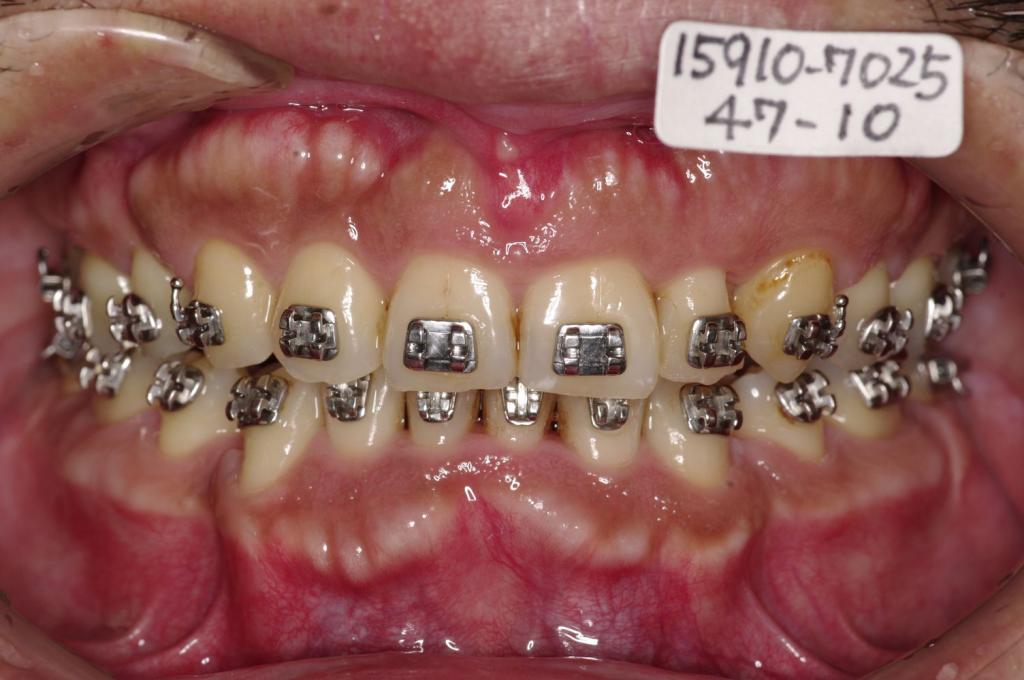

治療前

顎、顔の歪みの矯正治療前口内写真NO.525

装置の種類及び治療法 診断:顎変形症 下顎後退症 下顎右側偏位

治療方法および装置:マルチブラケット装置

High pull J-hook headgear

外科的矯正手術(健康保険適用)

抜歯:右上 4/左上5

右下 84/左下48